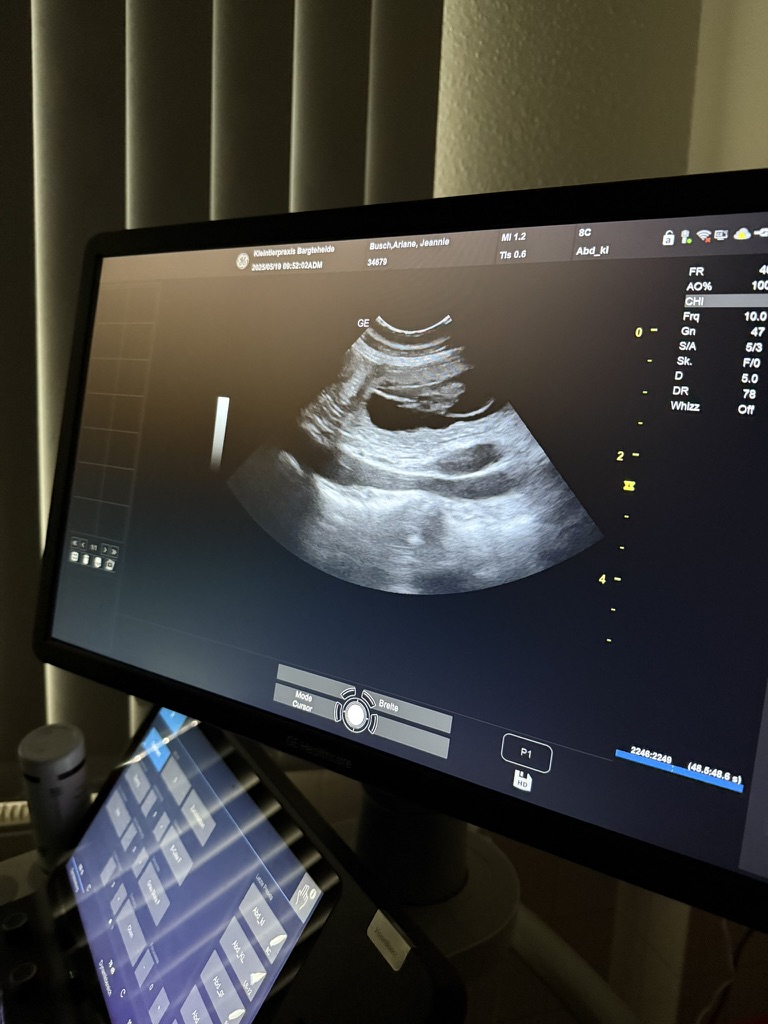

Unsere bezaubernde Jeannie „Tova‘s Riesling Surprise in Germany“ wurde Ende April von unserem charmanten Mio „Golden Nugget's Achilles“ gedeckt.

Wir erhoffen uns von dieser Verpaarung von zwei F3 Windsprites eine Erhöhung der genetischen Diversität mit den damit verbundenen positiven Auswirkungen auf die langfristige Gesundheit der Rasse. Apropos Gesundheit: Jeannie und Mio sind bereits 3,5 und 5,5 Jahre alt. Bis zur Zulassung der F3 Silken Windsprites hat es ja bekanntlich einige Jahre gedauert. Positiv daran ist, dass wir wissen, dass beide Hunde eine phantastische Konstitution und Gesundheit haben. Beide sind körperlich total fit und wirklich robust und unempfindlich – eigentlich waren sie noch nie richtig krank und vertragen jedes Futter.